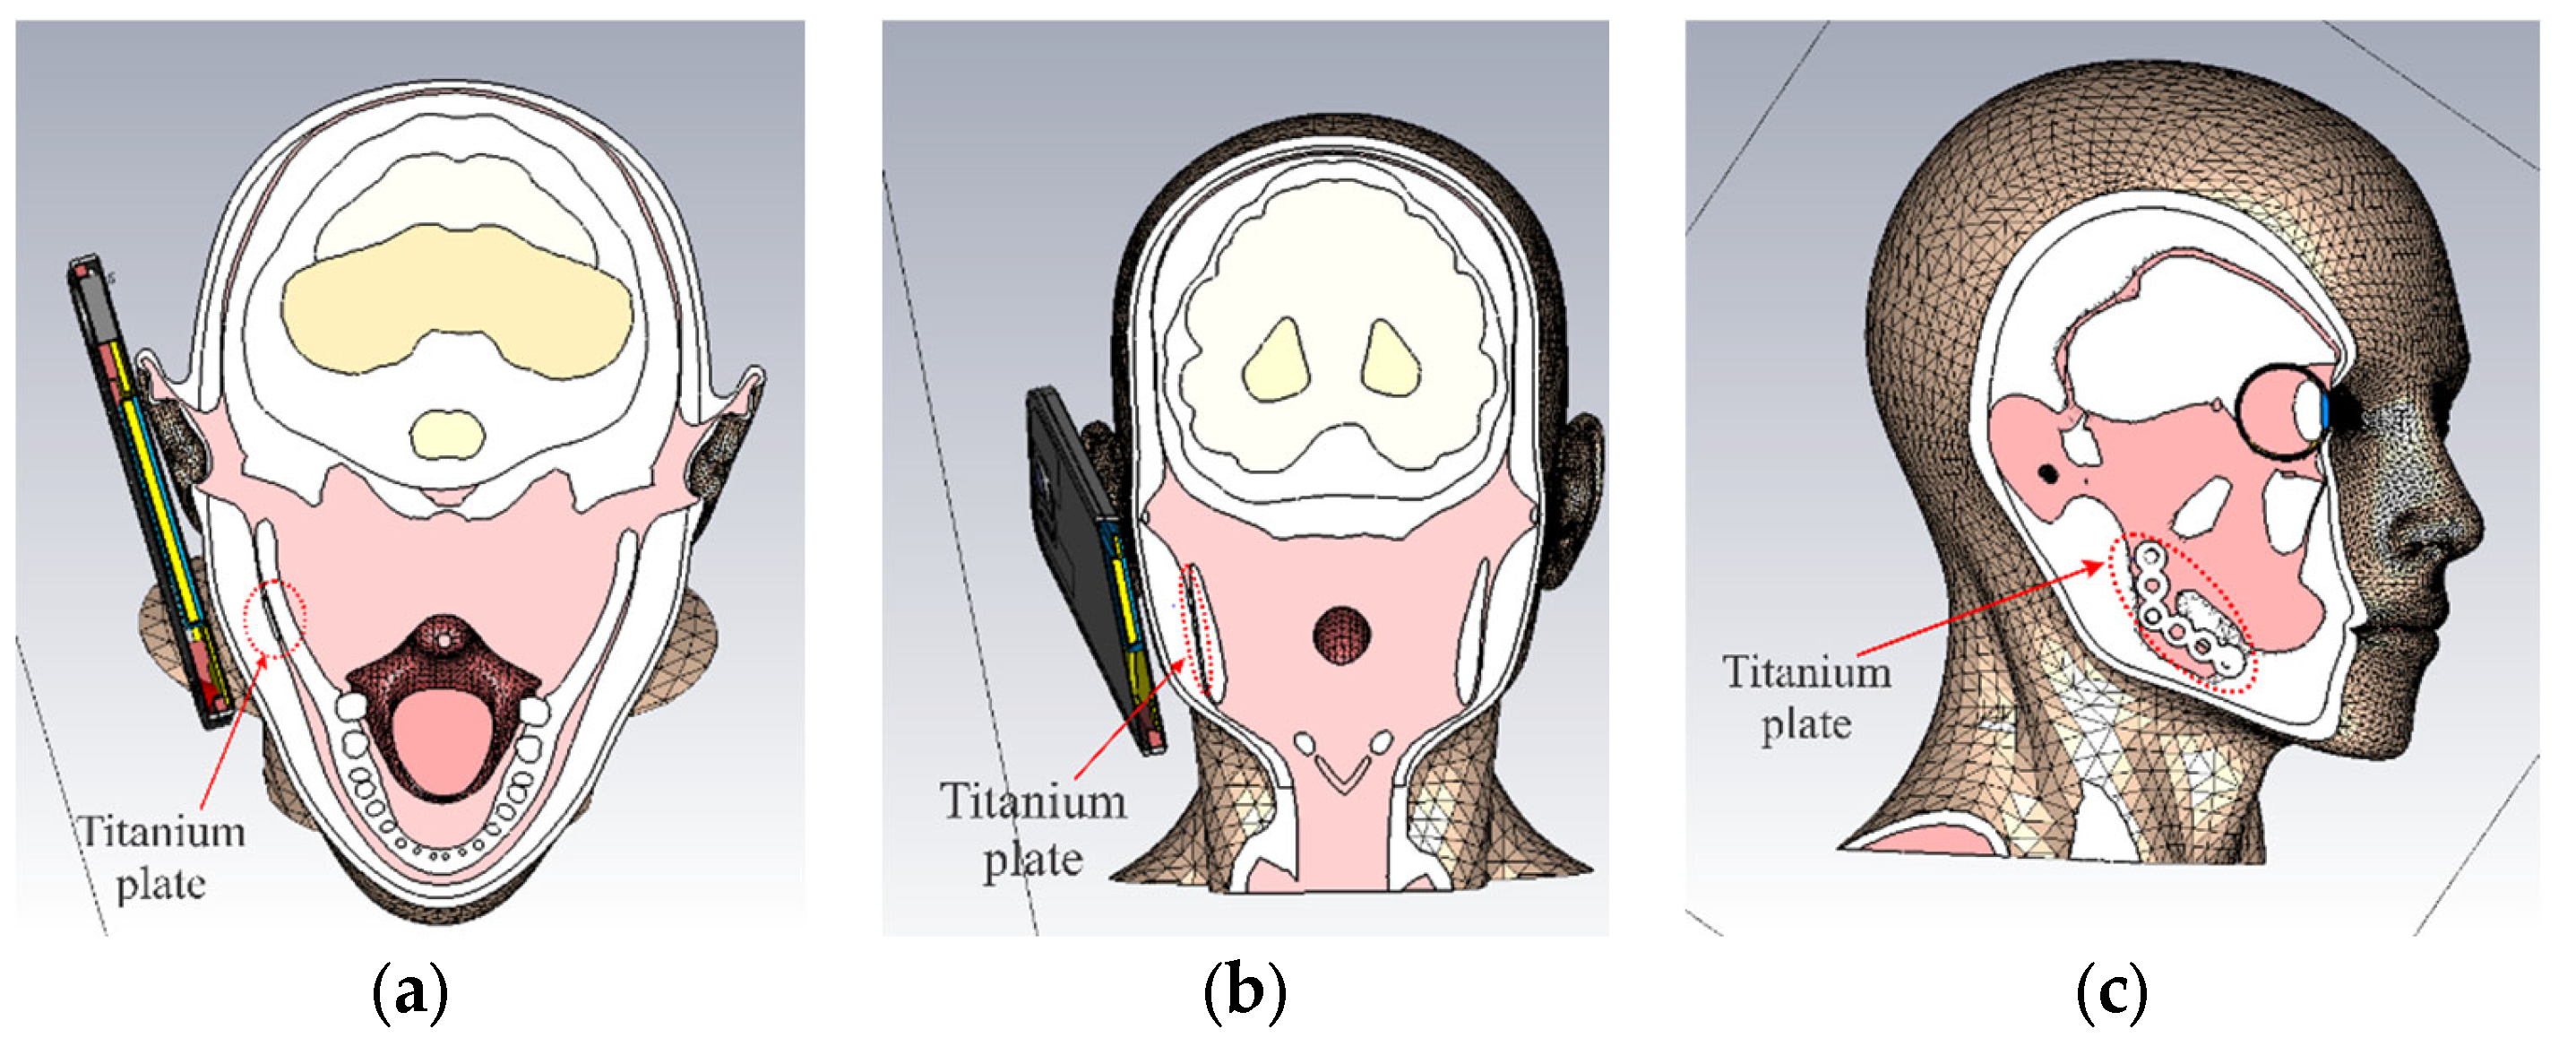

2.3. 3D Models of Titanium Plates and Screws

2.4. 3D Model of a Mobile Phone

3.1. Electric Field Distribution Inside the User’s Head

3.2. Distribution of SAR Values Within the Model of the Head of a User

3.3. Impact of the Face-to-Phone Distances on the Electric Field and SAR Distribution in the Implant Vicinity